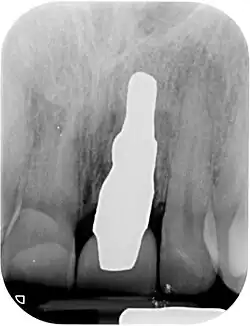

RAIs are custom made to perfectly fit the tooth socket of a specific patient immediately after tooth extraction. Therefore every implant is unique. As an optimised root-form it is much more than a simple 1:1 replica of a tooth. Since it exactly fills the gap left after the tooth is extracted, surgery is rarely needed. The implant can be produced from a copy of the extracted tooth, an impression of the tooth socket, or from a CT scan or CBCT scan.[7] The advantage of a CBCT scan is that the implant can be produced before extraction. With the former methods, it takes one or two days to fabricate an implant.

A root analogue implant can be fabricated from zirconium dioxide (zirconia) or titanium.[8] Successful titanium RAIs have been three-dimensionally printed as porous one-piece implants, using CAD software.[9] However, zirconia is the preferred material, because it is more esthetic in colour, with no grey discolouration visible through gums.[10][5]

- Obtain the 3D form of the tooth to be replaced. This is done either through careful tooth extraction and scanning of the root, taking an impression of the tooth socket, or a pre-op CBCT scan. The root analogue implant is produced using modern CAD/CAM technology, based on the principle of differentiated osseointegration;

- Atraumatic extraction of the hopeless tooth;

- Placement of the root analogue implant by tapping it in. In general, no surgery is necessary. In particular, no sinus lift or invasive surgery is ever necessary. The implant is placed immediately if it has been produced beforehand from a CBCT scan, or the next day if root has to be scanned or an impression of the socket is used. A protective splint is fitted to protect the implant during the healing period.

- Natural form: a custom milled anatomic implant replicates the natural form of a tooth, so it simply fits into the tooth socket. Like the original tooth, a root analogue implant can have single- and multi-rooted forms.